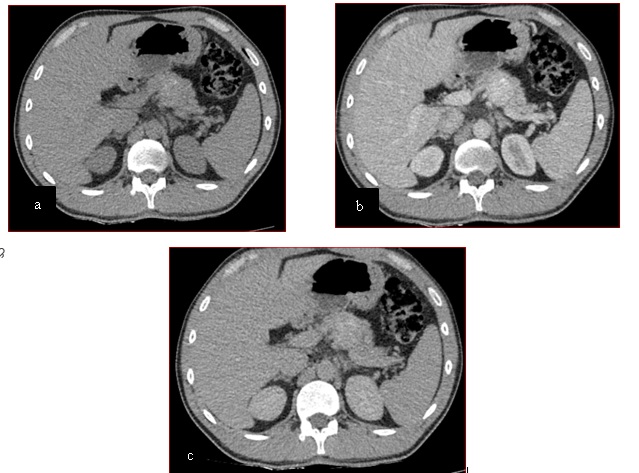

Tomografía de abdomen y pelvis con cte ev: del 13/10/2023.

Complicaciones posquirúrgicas

Tomografía de abdomen con cte ev: del 20/10/2023.

Tomografía de abdomen con cte ev: del 26/10/2023.

Estudio histopatológico reveló neoplásica de estirpe neuroendocrina bien delimitada.